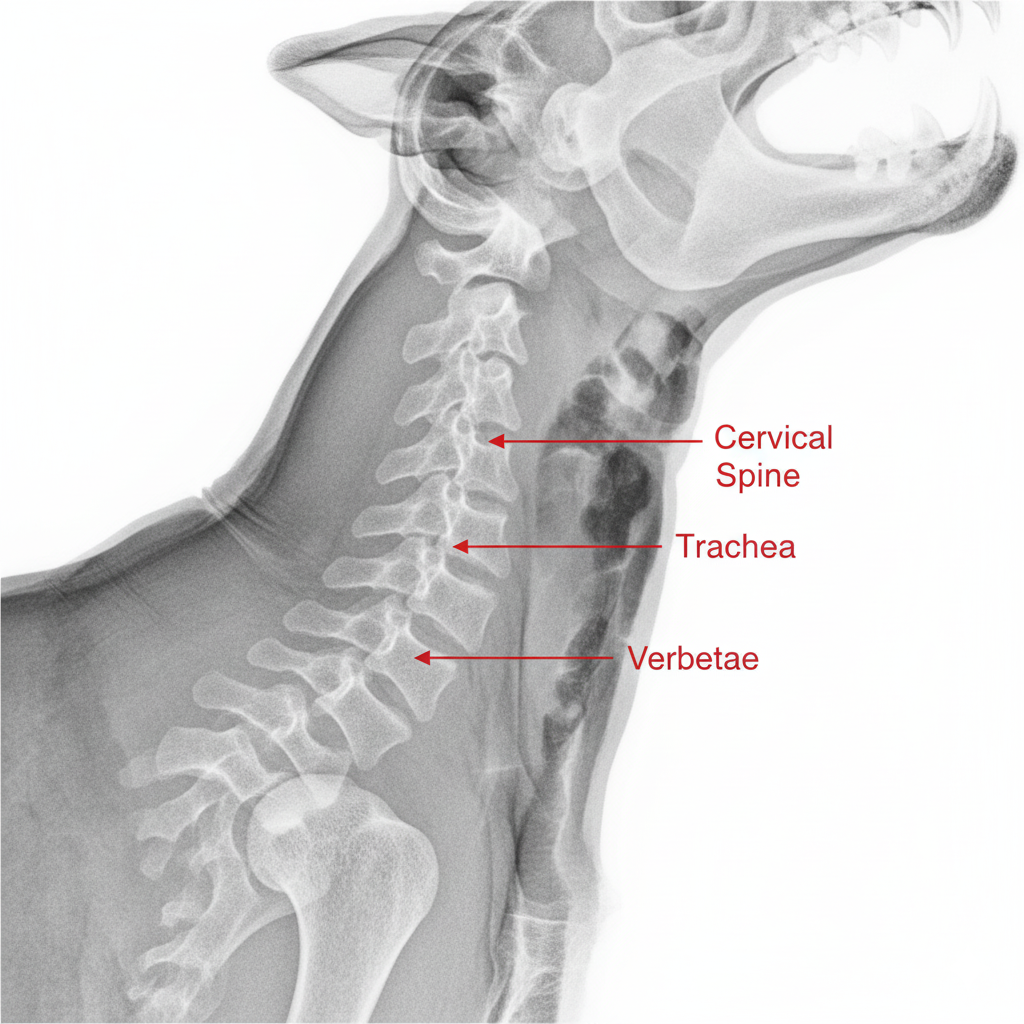

A choke chain is dangerous because it concentrates all leash pressure on the most vulnerable parts of your dog's neck. This can easily damage the trachea, esophagus, thyroid gland, and cervical spine. Misuse, which is incredibly common, can cause permanent injury or even death.

From a product design perspective, the choke chain is a flawed and dangerous tool. A dog's neck is a complex highway of vital structures. When you jerk a choke chain, you're not just giving a "correction"; you're delivering a sharp blow to their airway and spine. It's like trying to steer a car by hitting the engine with a hammer. The potential for damage is immense. Even when not actively "correcting," the constant pressure can restrict blood flow and increase pressure in the eyes, which is especially dangerous for certain breeds. The tool works through pain and the fear of pain. This is the exact opposite of the trust-based relationship we should be building with our dogs. My job is to design products that solve problems safely, and the choke chain fails that test on every level.